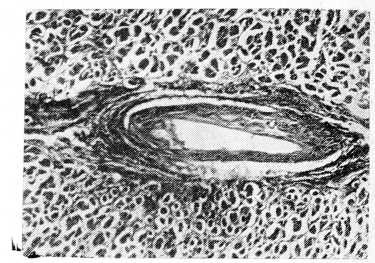

Гистологическая картина варьировала в зависимости от длительности болезни и в меньшей степени от этиологической специфики. Основой процесса являются дистрофические и некротические изменения миоцитов, начиная от зернистой дистрофии и до цитолиза; ряд мышечных волокон подвержен контрактурному сокращению, фрагментации и мелкоглыбчатому распаду (см. рис. 1).

Рис. 1. Фрагментация и мелкоглыбчатый распад мышечных волокон. Мужчина 54 лет. Окраска гематоксилин-эозином.×400.